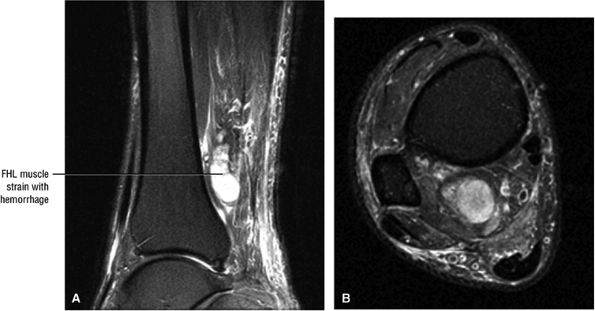

FIGURE 5.9 ● FLEXOR HALLUCIS LONGUS The flexor hallucis longus (FHL) flexes the great toe and plantarflexes the foot. The FHL is susceptible to injury during extremes of ankle plantarflexion and metatarsophalangeal dorsiflexion. The proximal sheath, 10 to 12 cm in length, has no mesotenon and may communicate with both the ankle joint and the sheaths of the flexor digitorum longus and tibialis posterior.